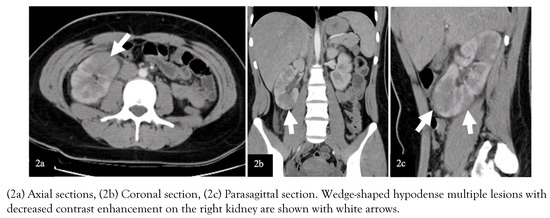

Introduction: Acute suppurative thyroiditis (AST) is an uncommon but potentially life-threatening condition. The majority of AST cases are caused by bacterial infection. Streptococcus suis is a swine pathogen that mostly causes meningitis and septice...